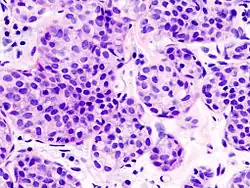

| Classical | 40% | Round or ovoid cells with little cytoplasm in a single-file infiltrating pattern, sometimes concentrically giving a targetoid pattern |

|

| Pleomorphic | Classical-appearing but with pleomorphic cells. It may include signet-ring cells, or plasmacytoid cells (pictured) which have abundant cytoplasm and eccentric nuclei. | ![]() |

Histopathology of invasive lobular carcinoma (ILC), next to lobular carcinoma in situ (LCIS) -

Invasive lobular carcinoma demonstrating a predominantly lobular growth pattern -

Lobular breast cancer. Single file cells and cell nests. -

ILC may be subtle on low magnification (left). Higher magnification (right) shows invasive growth pattern and vesicular nuclei with prominent nucleoli.